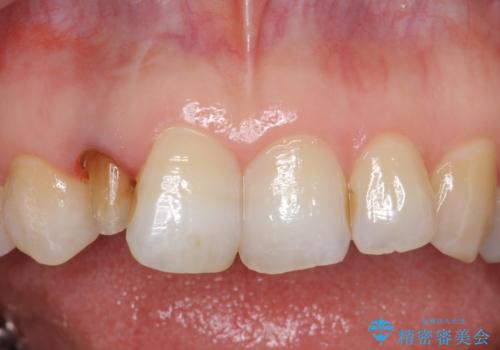

- 右上2番目の歯の変色が気になるといらっしゃった方の症例です。

再根管治療終了後、オールセラミッククラウンによる補綴を行いました。

今回用いたオールセラミッククラウンはジルコニアフレームという白い素材の上にセラミックを盛っているため、審美性が非常に高いのが特徴です。